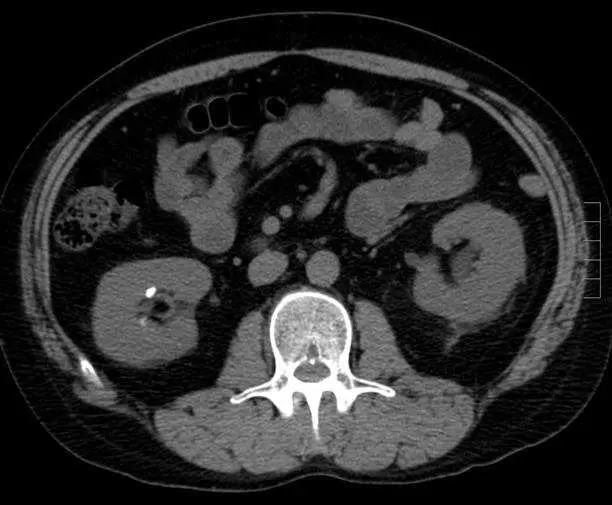

33 歲男性因陣發性腹痛而求醫,患者體溫正常、生命徵象穩定,患者接受對比劑注射前( pre-contrast )的電腦斷層掃描檢查如圖,下列診斷何者最恰當? 圖片描述

從所給的橫截面非造影腹部CT影像觀察到:

• 右側腎臟(影像左側)集合系統處有一亮白色高密度點狀影像,邊緣清晰、形狀圓形。

• 該高密度病灶 HU 值遠高於周邊腎實質(一般鈣質結石密度約 400–600 HU),符合結石呈現(Radiopaedia: CT 上 calcium oxalate 石 400-600 HU;99% 結石在 non-contrast CT 可見)(radiopaedia.org)。

• 腎周未見明顯腫脹或脂肪模糊,無大片水腫或積液。

• 關於闌尾與膽囊:闌尾位置(右下腹)未見增厚腸壁或脂肪混濁;右上腹膽囊形態、壁厚、周圍無滲出液,故不支持闌尾炎或膽囊炎。

• 腸胃道亦未見明顯積氣或液平面、無局部腸壁增厚。